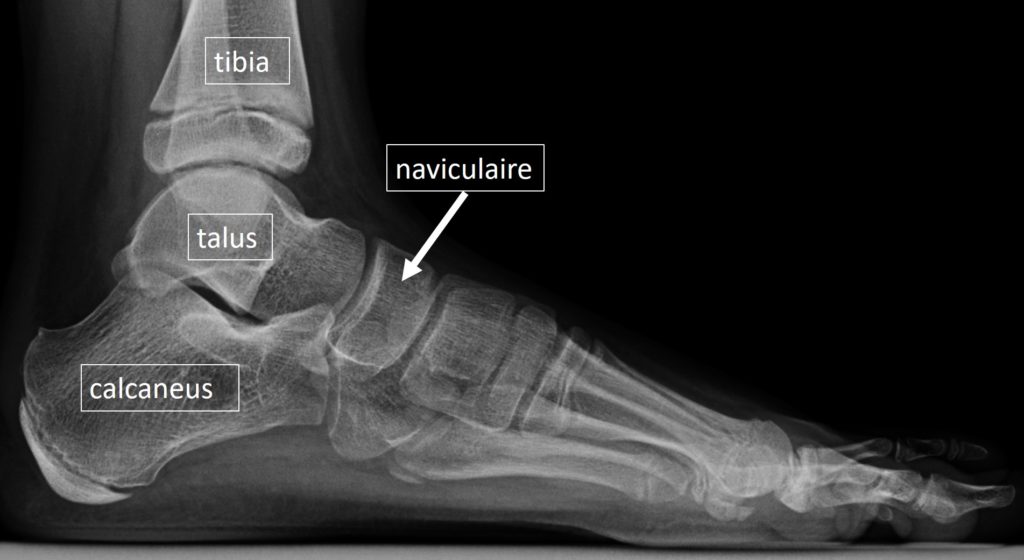

L'os naviculaire, situé dans le pied, est l'un des nombreux os qui composent l'articulation de la cheville Il fait partie de la voûte plantaire et joue un rôle essentiel dans la stabilité du pied

Source: litorageysw.pages.dev Navicular Bone Pain Causes And Treatment Cellaxys , L'os naviculaire est une petite structure osseuse située dans la partie médiale du pied, entre le talus et les os cunéiformes Ces douleurs sont souvent étiquetées à tort entorses de cheville en raison de leur localisation proche de la.